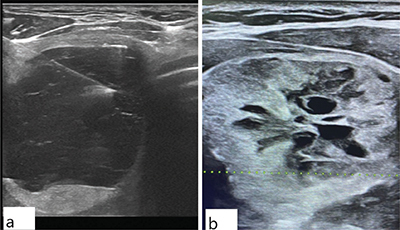

Objectives: This study aimed to investigate ultrasound (US) features of thyroid nodules categorized as nondiagnostic (ND) and atypia of undetermined significance (AUS) according to the Bethesda System for Reporting Thyroid Cytopathology (TBSRTC) and their potential implications for clinical management.

Materials and methods: A retrospective study was conducted on patients who underwent thyroid nodules FNAC between 2019 and 2023. Nodules falling into the ND and AUS categories were analyzed for US features, nodule size, composition, echogenicity, shape, margin, echogenic foci, the distribution of the American College of Radiology's Thyroid Imaging Reporting and Data System (ACR TI-RADS) categories, and other parameters. The study included a total of 1,199 patients and 1,252 nodules (ND: 1110; AUS: 142).

Results: No significant differences in age, gender, nodule features, echogenicity, shape, margin, echogenic foci, TI-RADS scores, localization, number of nodules, or thyroid parenchymal disease presence were found between the ND and AUS categories (p > 0.05). Also, no statistically significant difference in nodule size (<10 mm vs. ≥10 mm) existed between the ND and AUS categories (p = 0.475). Both showed predominantly solid composition and hyperechoic/isoechoic echogenicity. High proportions of TI-RADS 4 nodules were observed in both groups, with 727 (65.5%) in ND and 95 (66.9%) in AUS.

Conclusion: This study found no statistically significant differences in US characteristics between the ND and AUS categories, indicating potential similarities in their radiological appearances. Also, no significant difference in nodule size (<10 mm and ≥10 mm) was observed between these categories. Clinical management should consider further investigations, including repeat FNAC, due to the diagnostic challenges and malignancy risk in both categories.